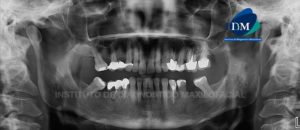

Paciente masculino de 56 años de edad acude al Instituto de Diagnóstico Maxilofacial por molestia en zona molar de lado izquierdo. A la evaluación panorámica